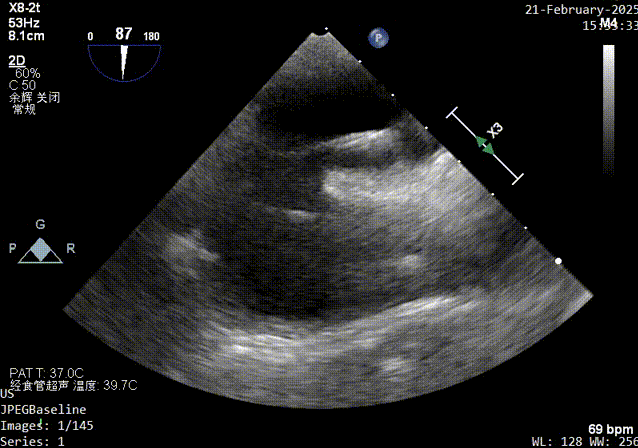

建立通路超声影像

继发隔缝合过程超声影像

继发隔捕获超声影像

继发隔穿刺缝合超声影像